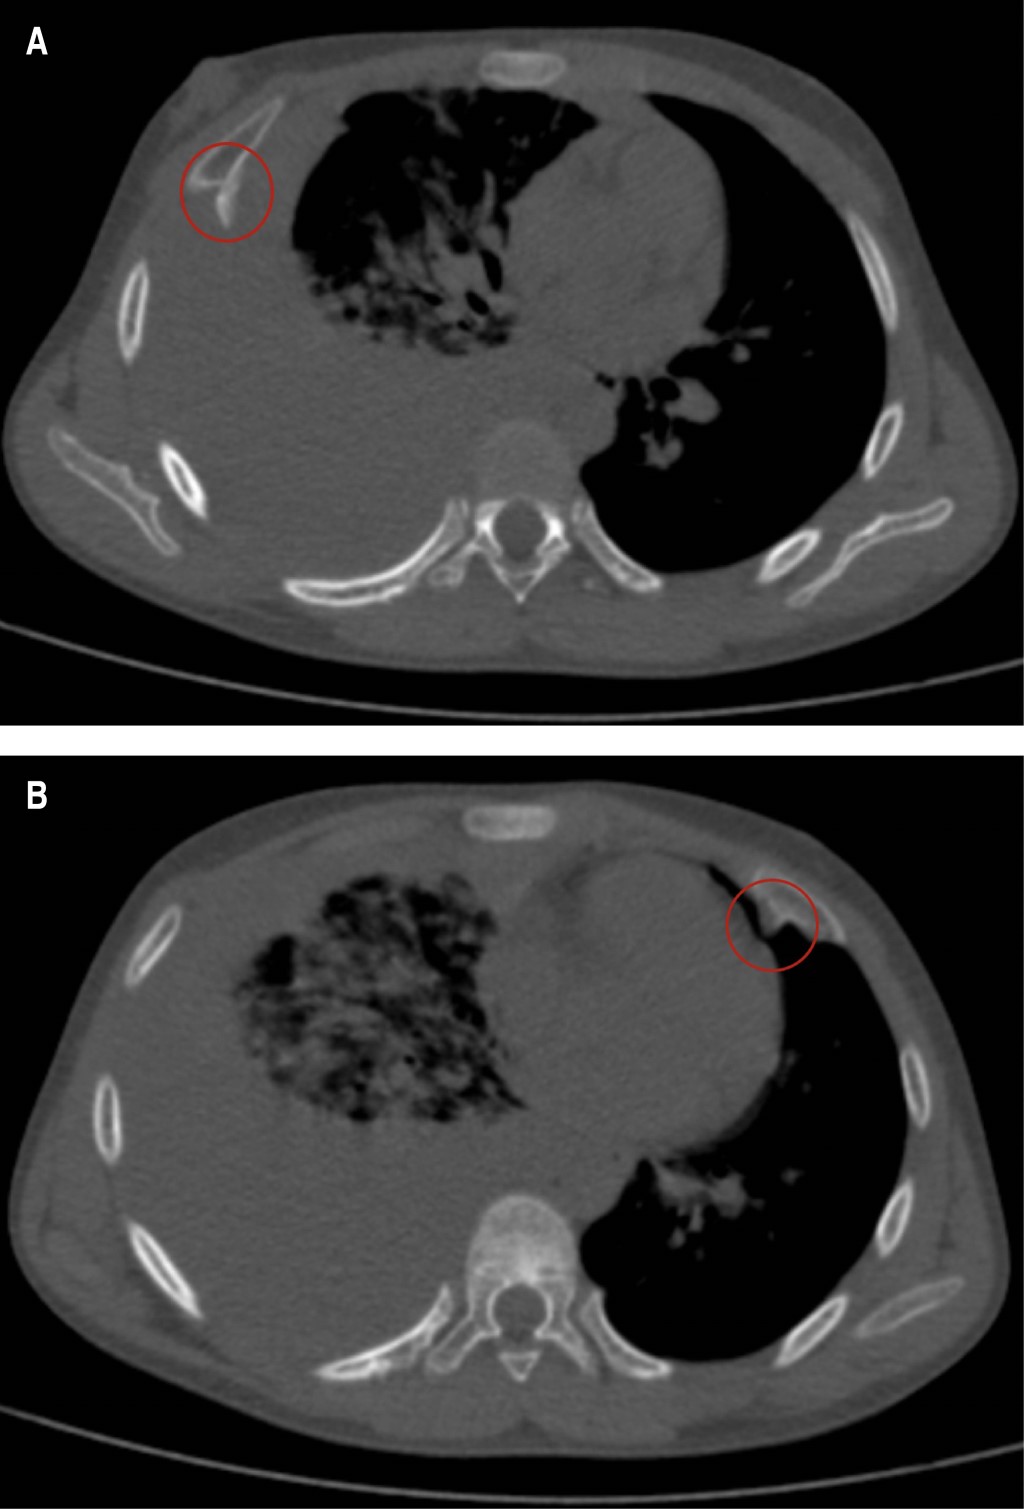

Exostosis costal como causa infrecuente de hemotórax. A propósito de un caso